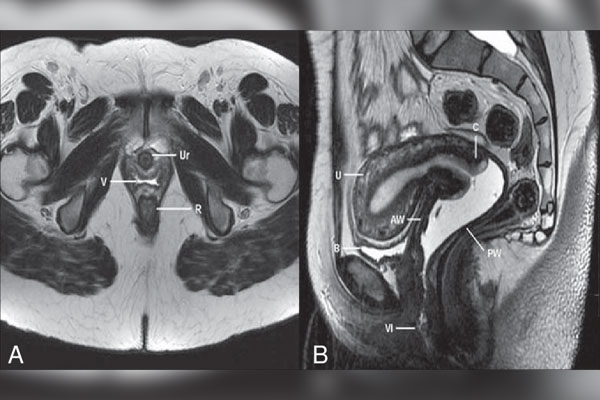

نوبت دهی ام آر آی کف لگن

ام آر آی کف لگن از امواج مغناطیسی و امواج رادیویی برای تصاویر با کیفیت بالا و دقیق از ساختارهای کف لگن استفاده میشود....